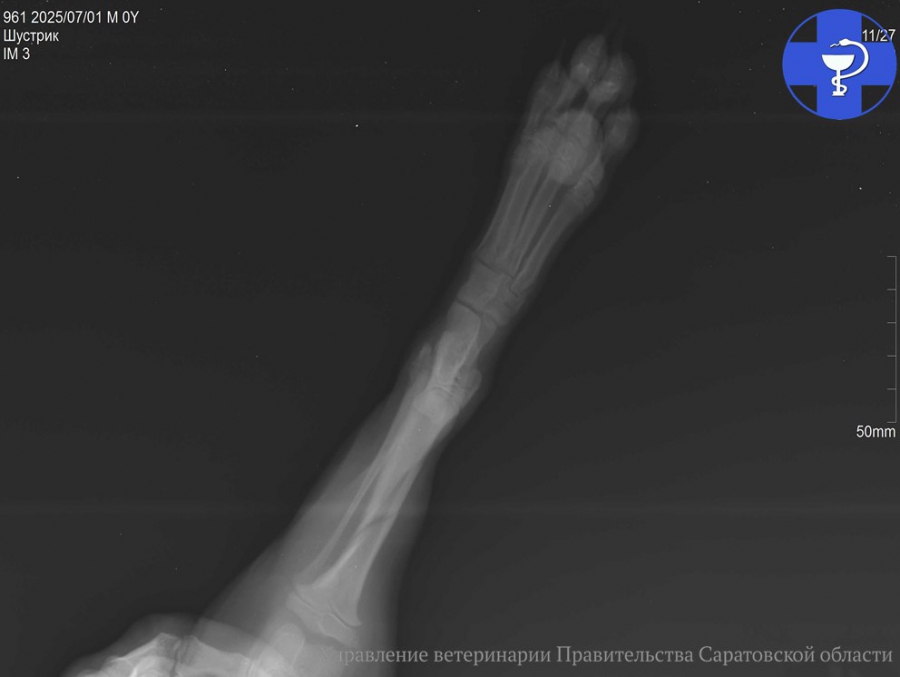

Сообщается, что в ветлечебницу обратилась хозяйка щенка по кличке Шустрик. Она пожаловалась на снижение активности и хромоту питомца на левую тазовую конечность. После тщательного клинического осмотра и получения всех необходимых данных от владелицы, Шустрику назначили рентген-диагностику. Обследование выявило косой оскольчатый перелом большеберцовой кости, что и стало окончательным диагнозом.